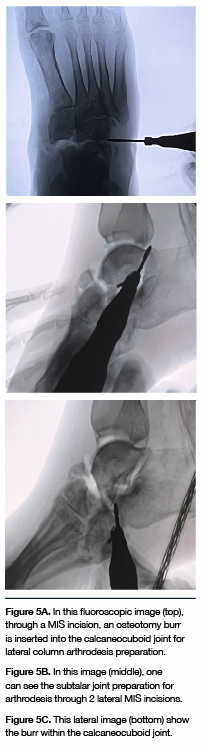

Case 2. A 45-year-old with bilateral Charcot midfoot collapse underwent MIS joint preparation for Charcot reconstruction due to a preulcerative plantar midfoot hyperkeratotic lesion. The patient had prior reconstruction on the left foot by another surgeon and had many complications with skin and bone healing, including osteomyelitis, hardware failure and wound dehiscence with a traditional extensile incision approach performed. The patient subsequently developed Charcot deformity of the right foot. Due to a history of wound healing complications, a MIS approach was chosen to prepare the medial column, lateral column and subtalar joints.

Due to dislocation and necrosis of the navicular bone, a separate incision was made to remove the bone with a saw blade. The other larger than MIS incision was for insertion of the medial column intramedullary nail. The patient has had no wound dehiscence or wound healing complications at the MIS sites, but did have superficial dehiscence at the non-MIS sites.